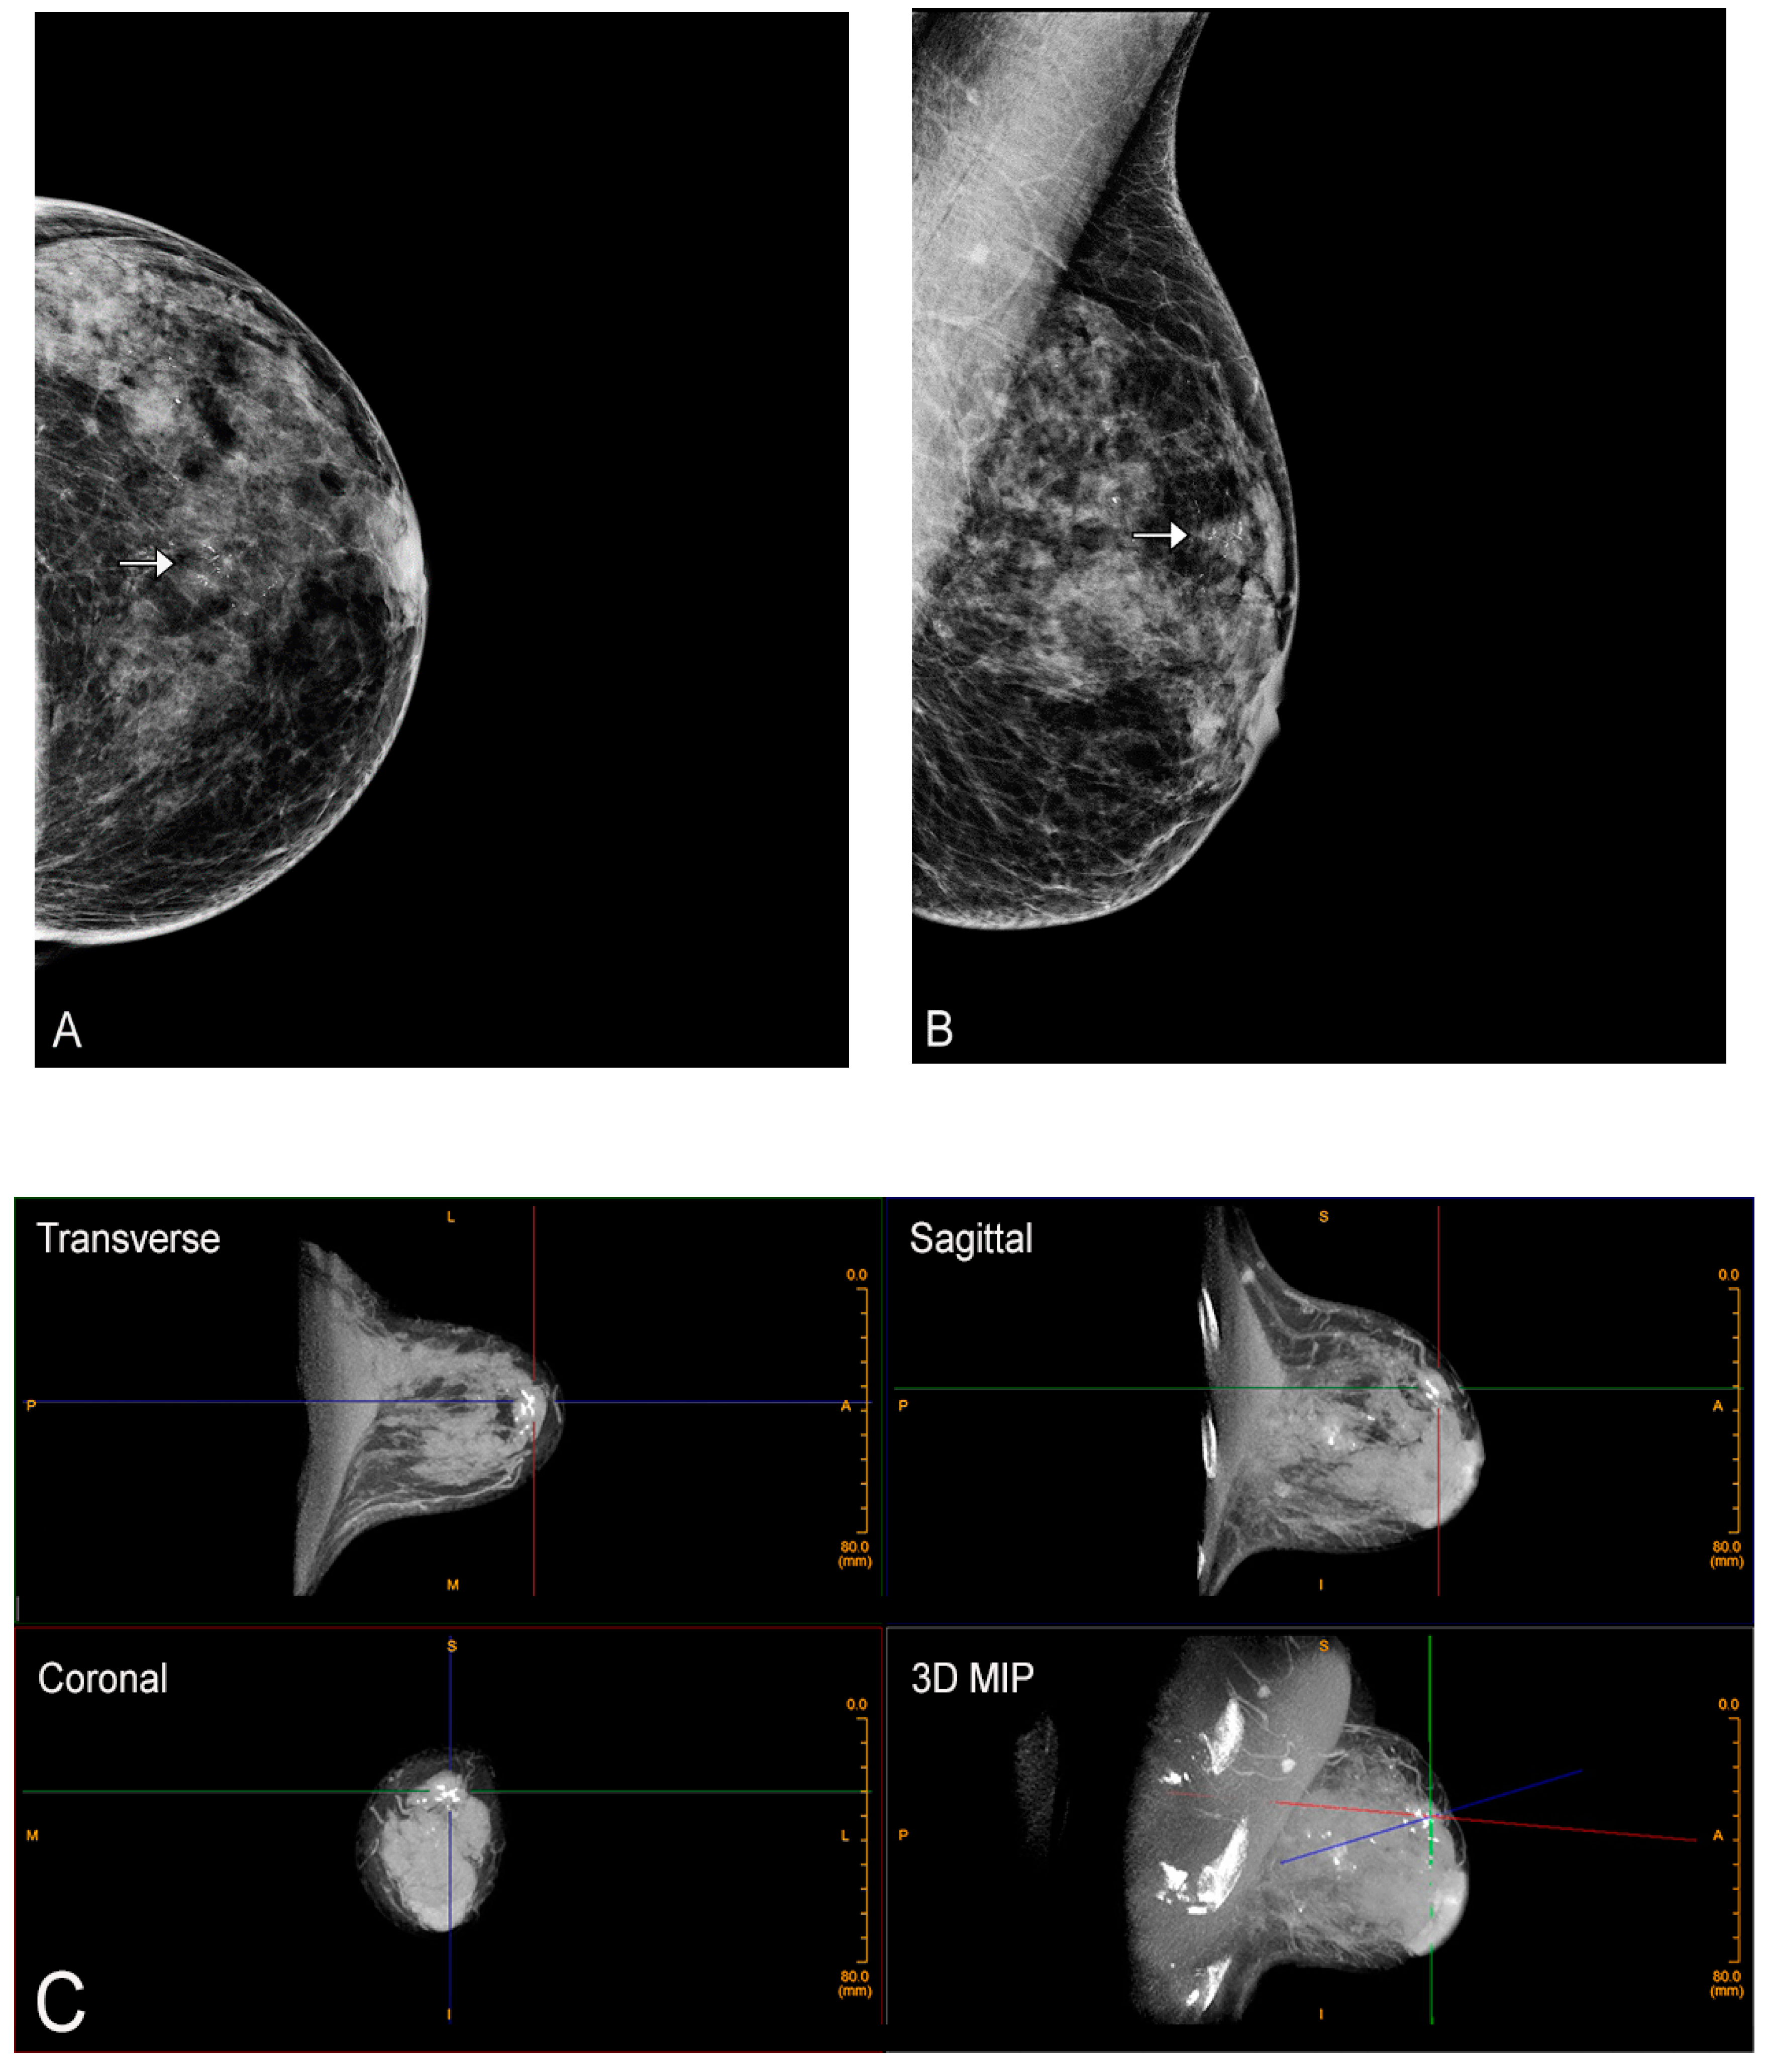

Figure 1.

Limitation of mammography for dense breasts. Bilateral craniocaudal (CC) (A) and bilateral mediolateral oblique (MLO) (B) mammograms showing extremely dense breasts (ACR density category d) [7]. The mammogram is negative (Breast Imaging Reporting and Data System (BI-RADS) 1). (C) Fortunately, the patient had a screening ultrasound shortly thereafter showing a 1 cm cancer at the 10 o’clock position in the right breast. The mammogram was a false negative. The patient came to no harm since the ultrasound was performed within a short period of time. The cancer was grade I invasive ductal carcinoma with negative nodes. Survival after treatment is near 100% [8].